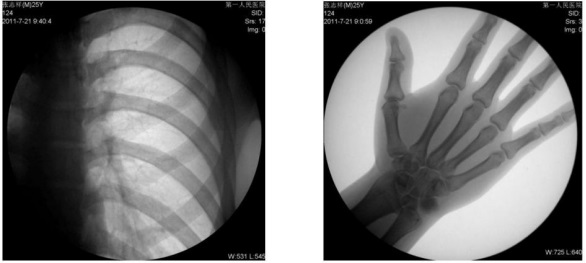

1、數(shù)字化透視:適用于全身各部位透視(如胸透、腹透等)。

動(dòng)態(tài)采集速度≥25 幀/秒,主要應(yīng)用于臨床各科室,尤其是體檢科、內(nèi)科、外科、骨科、創(chuàng)傷科、急診科等。

1) 胸部檢查:能實(shí)現(xiàn)全胸透視動(dòng)態(tài)觀察,對(duì)于需要在透視下動(dòng)態(tài)觀察的病變,如肺部腫瘤、氣管異物等可進(jìn)行實(shí)時(shí)點(diǎn)片。胸部透視是體檢中的常規(guī)檢查項(xiàng)目,臨床意義在于檢查有無(wú)肺癌, 特別是早期肺癌。使用胃腸機(jī)可通過(guò)胸部透視雙肺,縱膈有無(wú)病變,以確定病變部位的部位、大小、密度,與周邊組織關(guān)系,常見的疾病,如肺炎、肺結(jié)核等。胃腸機(jī)可以從各種角度動(dòng)態(tài)詳細(xì)觀察肺、心臟或其他胸部的病變,對(duì)病變的情況可以有個(gè)比較全面地了解。